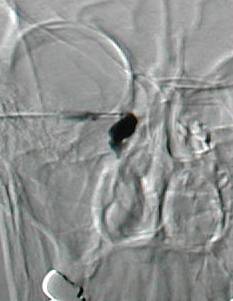

Left DCG showing  lacrimal sac filling  followed by spillage of the dye into the nasal cavity through the patent dacryocystorhinostomy.